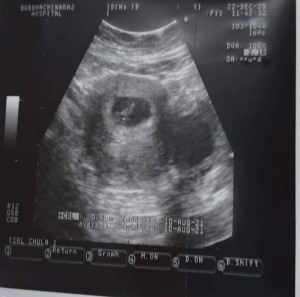

ตรงกลางใช้ตัวอ่อนมั้ยค่ะU/Sครั้งแรกตอน7WeeKสอบถามแม่ๆหน่อยค่ะ

ใช่ค่ะ น่าจะ 0.9 cm ตัวหนังสือไม่ค่อยชัดค่ะ